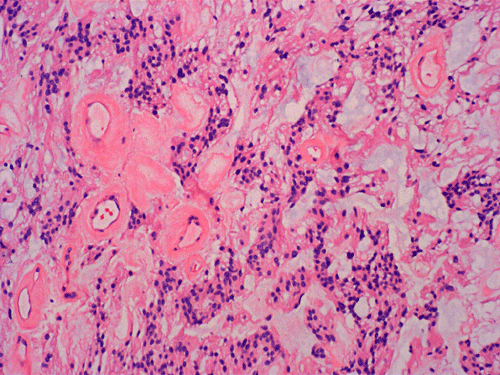

On cytologic preparations, there are clumps of tissue that do not smear out well (Panel A). On higher magnification, these tissue clusters are composed of large blobs of bluish, acellular, mucoid material admixed with cells with relatively uniform, bland nuclei and small amount of cytoplasm (Panel B). In the less tightly packed areas, the long cytoplasmic processes of the cells can be well appreciated (Panel C). These long processes are highly suggestive of a glial neoplasm. On frozen sections, the lesion is composed of multiple blobs of bluish, mucoid material surrounded by tumor cells (Panel D and E). Features of the paraffin sections are not that much different from that of the frozen sections (Panel F G H).

Histopathology: The salient feature of myxopapillary ependymomas is a rich, thin walled micropapillary bundle surrounded by a single of epithelium that varies from low cuboidal to columnar. The cells typically have rounded nuclei with a delicate, rather open chromatin and a moderate amount of amphophilic cytoplasm. The cores of the papillae consist of blood vessels surrounded by a variable amount of mucinous matrix. The amount varies from small to substantial. The vessels are characterized by extensive thickening and hyalinization of the vessel wall. Ins some tumors, there are components with features of conventional ependymomas 24. Mitotic activity is very low or absent 25. Myxopapillary ependymomas usually have sharply defined margins, although nerve roots may be enclosed. A proportion of tumors are surrounded by a condensed connective tissue capsule 11.